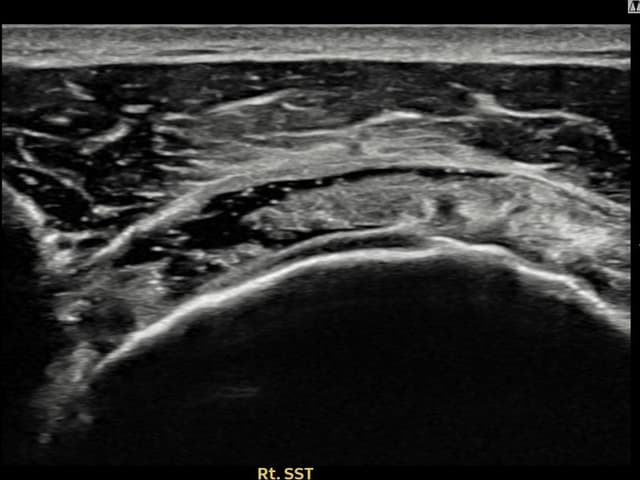

[촬영시기:23.09.09~23.12.15]

[어깨인대 축소봉합술] 우측 어깨 통증으로 수면과 일상 동작이 어려워 내원하셨습니다.